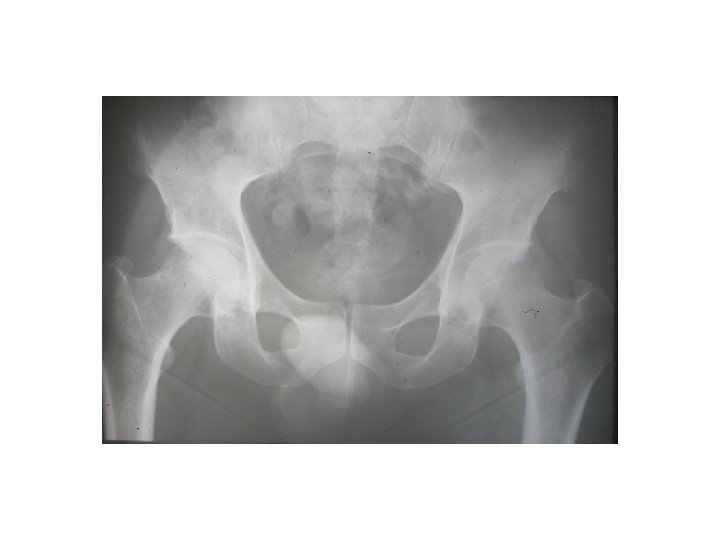

SEMIOLOGIE DE LA HANCHE J-P ESCHARD • Anatomie Articulation profonde Articulation très emboîtée mobilité

SEMIOLOGIE DE LA HANCHE J-P ESCHARD • Anatomie Articulation profonde Articulation très emboîtée mobilité réduite

SEMIOLOGIE DE LA HANCHE 3°Signes d’examen (signes physiques): Inspection: a) Étude de la marche

SEMIOLOGIE DE LA HANCHE 3°Signes d’examen (signes physiques): Inspection: a) Étude de la marche boiterie par esquive d’appui (visible et/ou audible) bascule du bassin (Trendelenbourg) b) Attitudes vicieuses réductibles ou non flessum RE

SEMIOLOGIE DE LA HANCHE 3°Signes d’examen (signes physiques): Etude des mouvements Mouvements passifs+++: le coxogramme flexion/extension/abduction/adduction RE/RI Mouvements combinés Mouvements actifs : étude des muscles et des tendons: le moyen fessier++ 4° Examen régional: neurologique amyotrophie